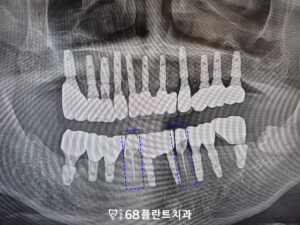

먼저 치아를 발치 후

임플란트를 식립 하였습니다.

임플란트는 식립하고

바로 끝나는 게 아니라

치유기간을 기다린 뒤

보철 작업이 들어가기 때문에

그동안 아래 송곳니

신경치료를 진행하였습니다.

이후 임플란트가 뼈에 잘 달라붙고

치유가 되어,

보철 작업을 시작하였습니다.

그리고 기존 임플란트의 보철을 모두 제거한 후,

전체적으로 함께 보철물을

새롭게 제작하여

임플란트와 송곳니의 조화로운 기능과

미소를 완성하였습니다.